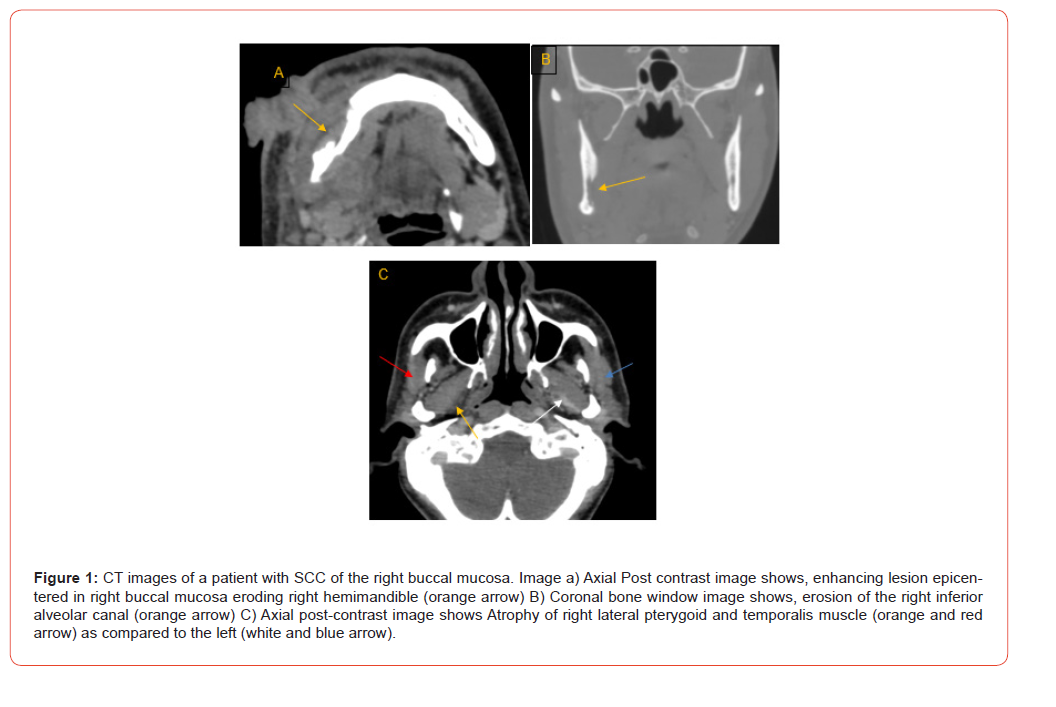

24 out of 100 patients had PNS on CT (Table 6, Figures 1-5), whereas 26 of 100 patients had histopathologically proven PNS. The two methods agreed in 88.0% of the cases and disagreed in 12.0% of the cases. There was a statistically significant agreement between the two variables, with kappa value of 0.680. Sensitivity, specificity, PPV, NPV and diagnostic accuracy of CT images for the detection of PNS were 73.1%, 93.2%, 79.2%, 90.8% and 88% respectively (Table 7). The most common nerve involved was mandibular nerve followed by maxillary nerve. Strongest predictors of PNS included foraminal widening, nerve thickening, and muscle denervation (Table 8).

Analysis of TNM staging indicated that advanced-stage tumors (III and IV) showed a higher prevalence of PNS. However, statistically, no significant relation was seen between the T and N stage of tumour and presence of PNS (Figure 6 and 7). Anatomical patterns revealed that PNS was most common in the buccal mucosa, followed by tongue, retro-molar trigone, alveolus, gingiva-buccal sulcus and hard palate (Figure 8).